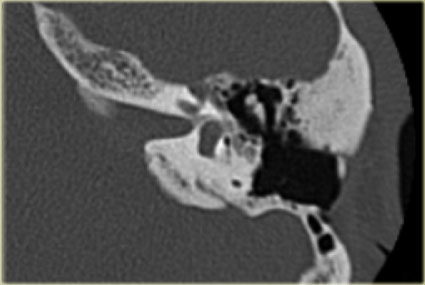

Bên trái là hình ảnh của một bé trai 2 tuổi với teo ống tai ngoài xương hai bên.

Xương búa và xương đe hợp nhất (mũi tên).

Ốc tai bình thường.